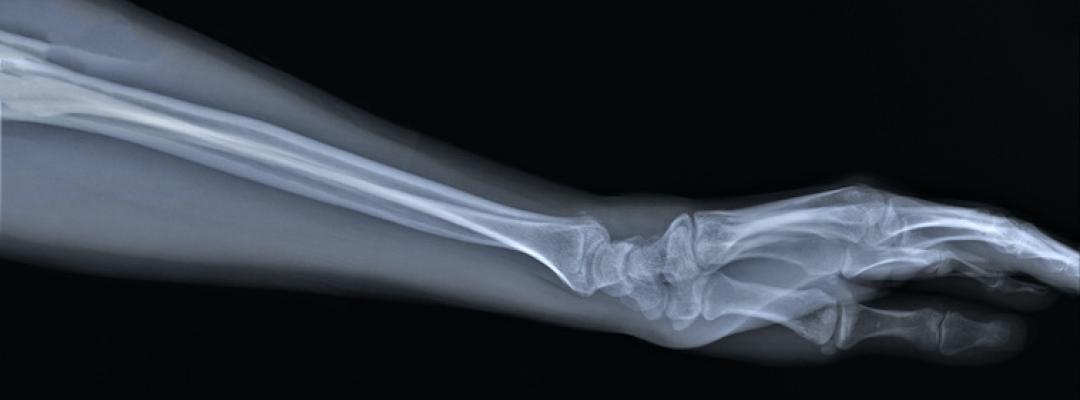

Die Entdeckung der Röntgenstrahlen: Ein Blick in die Lunge

Die Entdeckung der Röntgenstrahlen: Ein Blick in die LungeEnde des 19. Jahrhunderts entdeckte der Physiker Wilhelm Conrad Röntgen eher zufällig die nach ihm benannten Röntgenstrahlen. Bei unzähligen Anwendungen, wie auch beim Lungenröntgen, offenbart sich der unschätzbare Wert der Entdeckung, für die es den Nobelpreis gab.

Wilhelm Conrad Röntgen war als leitender Physiker am Institut für theoretische Physik an der Julius-Maximilians-Universität in Würzburg tätig, als ihm 1895 zufällig eine grandiose Entdeckung gelang. Er experimentierte mit den neu entdeckten Kathodenstrahlen, als ihm ein Stück Papier in die Hände fiel, das aufgrund der Beschichtung unter Kathodenstrahlen bzw. ultraviolettem Licht leuchtete. Röntgen nannte die neu entdeckten Strahlen „X-Strahlen“ und erkundete, welche Materialien sie wie stark durchdrangen. Die Hand seiner Frau war das erste Körperteil, bei dem er fasziniert feststellte, dass der Ring um den Knochen zu schweben schien. Schnell wurden die Röntgenstrahlen für alle möglichen Anwendungen eingesetzt, denn erst viel später erkannte man, dass sie auch Gefahren bergen. 1901 wurde Wilhelm Conrad Röntgen für seine Entdeckung mit dem Nobelpreis für Physik ausgezeichnet. (1)